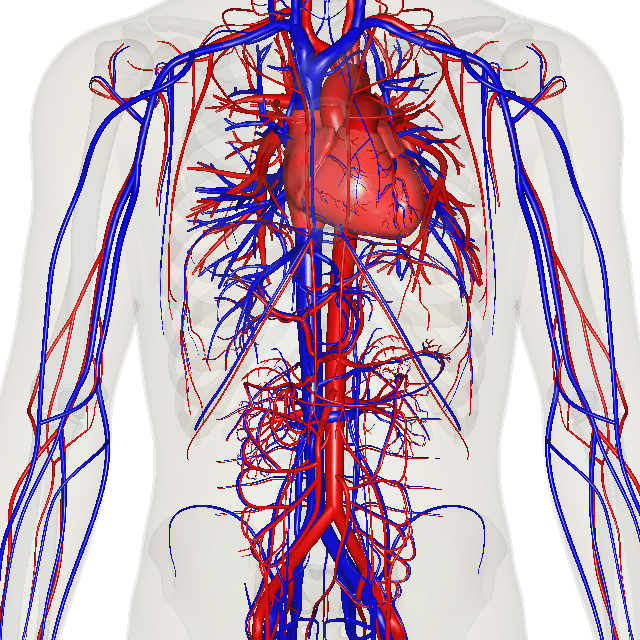

순환계는 심장, 혈관, 혈액으로 구성된다.[51] 모든 척추동물의 심혈관계는 심장과 혈관으로 구성되며, 순환계는 폐순환과 온몸순환으로 나뉜다.[52][53][54]

- '''폐순환'''은 우심실에서 산소가 부족한 혈액을 폐로 보내 산소를 공급받아 좌심방으로 돌려보내는 순환이다.

- '''온몸순환'''은 왼쪽 심장에서 신체의 나머지 부분으로 산소가 풍부한 혈액을 보내고 대정맥을 통해 산소가 부족한 혈액을 다시 오른쪽 심장으로 되돌리는 순환이다. 온몸 순환은 대순환과 미세 순환 두 부분으로 나눌 수 있다.

평균 성인의 혈액량은 약 4.7~5.7리터로, 전체 체중의 약 7%를 차지한다.[55] 혈액은 혈장과 혈구(적혈구, 백혈구, 혈소판)로 구성된다. 소화계는 순환계와 함께 작동하여 온몸 순환으로 심장 박동을 유지하는 데 필요한 영양분을 제공한다.[56] 이 외에도 관상동맥 순환, 대뇌 순환, 신장 순환, 기관지 순환이 있다.

인간의 순환계는 폐쇄형 순환계로, 혈액이 혈관망 내에 있다.[57] 영양소는 미세순환계의 작은 혈관을 통해 이동하여 장기에 도달한다.[57]

심장을 통해 온몸으로 나가는 혈액을 운반하는 혈관을 동맥이라 하고, 온몸에서 심장으로 들어가는 혈액을 운반하는 혈관을 정맥이라 한다. 모세혈관은 체조직과 혈액 사이에서 영양과 가스를 교환하는 장소이며, 매우 가늘다.[41] 혈관은 외막, 중막, 내막의 3개 층으로 이루어져 있다.[60]| 구분 | 동맥 | 정맥 | 모세혈관 |

2. 2. 1. 동맥

심장에서 나오는 혈액을 운반하는 혈관을 동맥이라고 한다. 동맥은 높은 혈압을 유지하며 심장의 박동에 따라 유연하게 팽창하고 수축된다. 산소를 운반하는 헤모글로빈에 의해 선명한 붉은색을 띤다.[60]

산소화된 혈액은 좌심실을 떠나면서 대동맥 반달판을 통해 전신 순환계로 들어간다.[15] 전신 순환의 첫 번째 부분은 거대하고 두꺼운 벽을 가진 동맥인 대동맥이다. 대동맥은 흉추 10번 척추 수준에서 횡격막의 대동맥 구멍을 통과한 후 아치형으로 굽어지고 신체의 상부에 혈액을 공급하는 가지를 낸 다음 복부로 들어간다.[16] 이후 아래로 내려가 복부, 골반, 회음부 및 하지에 가지를 공급한다.[17]

혈관계에서 폐로부터 돌아온 산소를 풍부하게 함유한 혈액은 동맥혈이라고 불리며, 이것은 심장이 박동함으로써 좌심실로부터 대동맥으로 밀려나 전신에 뻗어 있는 혈관으로 보내진다. 대동맥은 신체의 위쪽으로 향하는 상행 대동맥과 하반신으로 향하는 복부 대동맥으로 크게 나뉘며, 다양한 동맥으로 갈라져 더욱 세밀한 모세혈관으로 혈액을 보내 신체 조직에 산소와 영양분을 공급한다.[41]

2. 2. 2. 정맥

심장으로 들어가는 혈액을 운반하는 혈관을 정맥이라 한다. 정맥은 혈압이 낮고 동맥에 비해 유연성이 떨어진다. 헤모글로빈의 산소가 소진되어 어두운 붉은색을 띤다.[60] 정맥 벽은 일반적으로 얇고, 질감이 별로 없다. 혈압이 낮기 때문에 울혈과 역류가 일어나기 쉬운데, 이를 방지하기 위해 관 안에는 역류 방지 밸브 역할을 하는 주름 구조인 정맥판이 있다.[44]모세혈관은 세정맥으로 합쳐지고, 세정맥은 다시 정맥으로 합쳐진다.[22] 정맥계는 심장 위 조직을 주로 배출하는 상대정맥과 심장 아래 조직을 주로 배출하는 하대정맥의 두 개의 주요 정맥으로 흘러 들어간다. 이 두 개의 큰 정맥은 심장의 우심방으로 이어진다.[23]